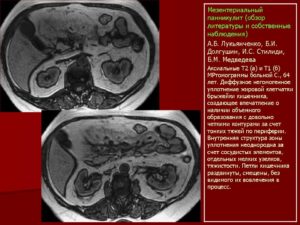

“Золотым стандартом” диагностики мезентериального панникулита считают магнитно-резонансную томографию и компьютерную томографию.

В результате исследования появляется возможность увидеть все деструктивные изменения структуры брыжейки, подкожно-жировой клетчатки, очаги уплотнения, фиброзной ткани и ограниченных опухолей.

Посредством МРТ или КТ можно своевременно выявить предраковые изменения вовлеченных в патологический процесс тканей.